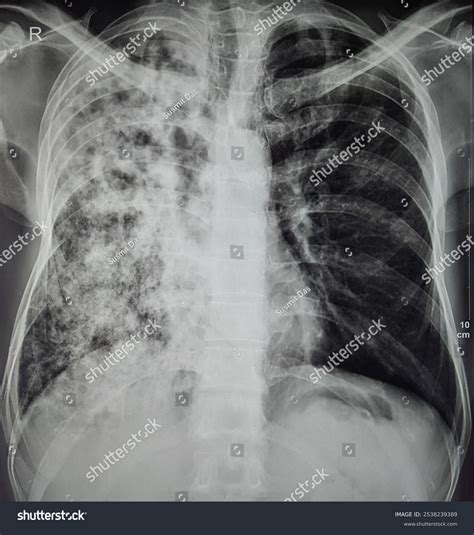

Interpreting Tb X Ray results requires expertise and experience. Radiologists look for specific signs that may indicate TB:

• Cavities: These are hollow spaces in the lungs that can form as the body tries to contain the infection.

• Nodules: Small, round opacities that can be indicative of TB infection.

• Infiltrates: Areas of increased density in the lung tissue, often seen in active TB.

• Pleural Effusion: Fluid accumulation in the pleural space, which can be a complication of TB.

It’s important to note that while Tb X Ray can provide valuable information, it is not always conclusive. Additional tests, such as sputum tests or CT scans, may be required for a definitive diagnosis.